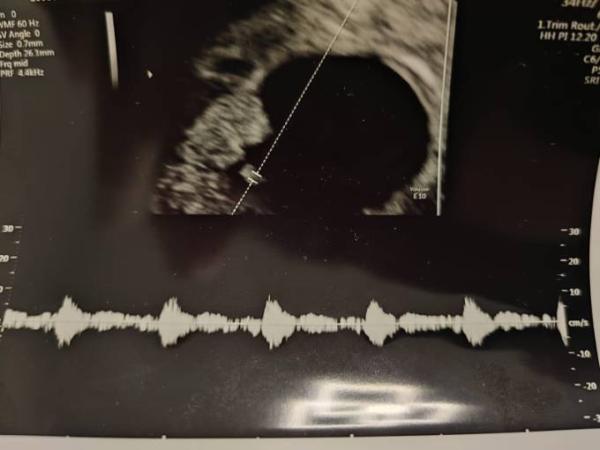

Ich war auch damals 5+1 beim FA und hat man genau die fruchthöhle gesehen war dann 8+3 wieder dort Im Anhang siehst du was man bei mir gesehen (8+3) hat ein Mini Mini Me und den ersten herzschlag dazu mittlerweile bin ich in der 33ssw..... Drück dir die Daumen

Bild zu